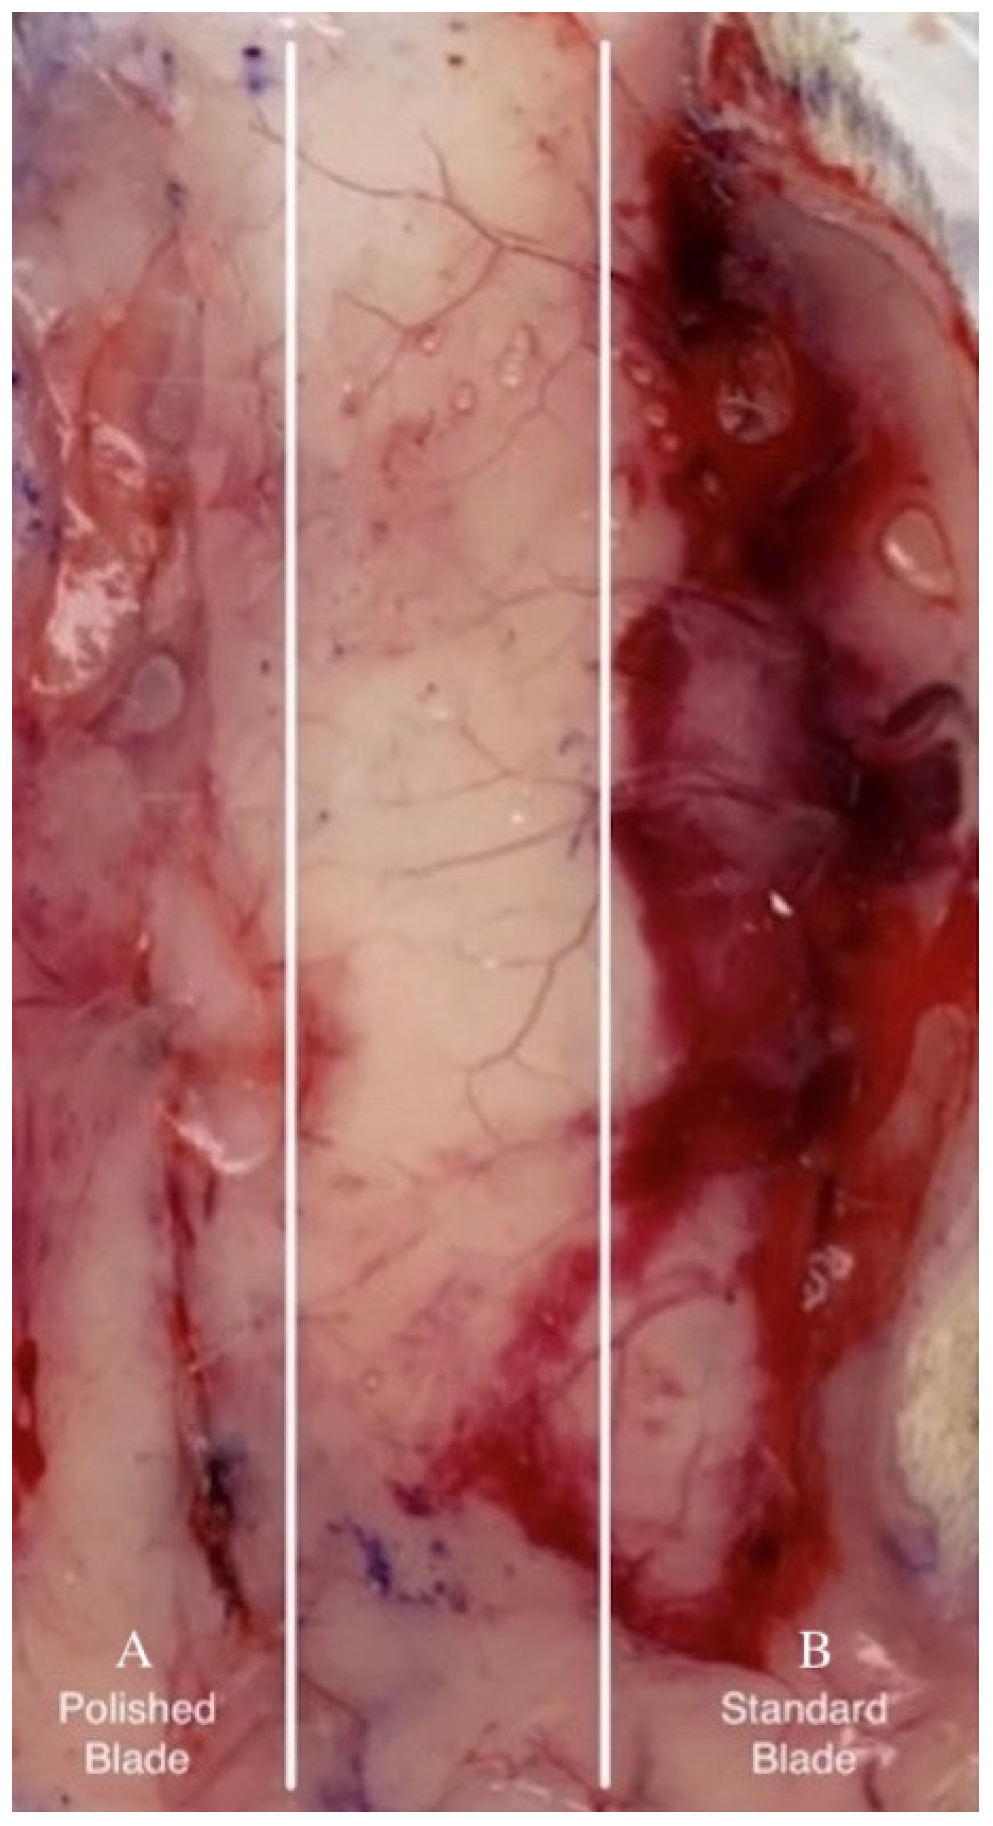

Morphometric wound analysis reveals site-specific differences in healing for the two types of incisions. While not quantified, in tissue samples collected 1 day after surgical incision, subcutaneous blood staining was frequently observed in incisions made with the SB and less frequently with the EB (Figure 3). Monitoring blood staining was not part of the experimental plan. Within 3 days after skin incisions, the majority of wounds produced by SB did not achieve closure (Figure 4). In contrast, approximately 90% of incisions made by EB exhibited adherence in this same period. The results show that the wound treated with SB did not close completely on the third day; however, the one treated with EB did. By day 7, all wounds achieved closure. After 2 months, all incisions were completely healed, and the dorsal skin softness and elasticity were qualitatively judged to be normal.

Figure 3.

Bleeding under tissue excised 1 day post-surgery: incisions made by EB (A) and SB (B).